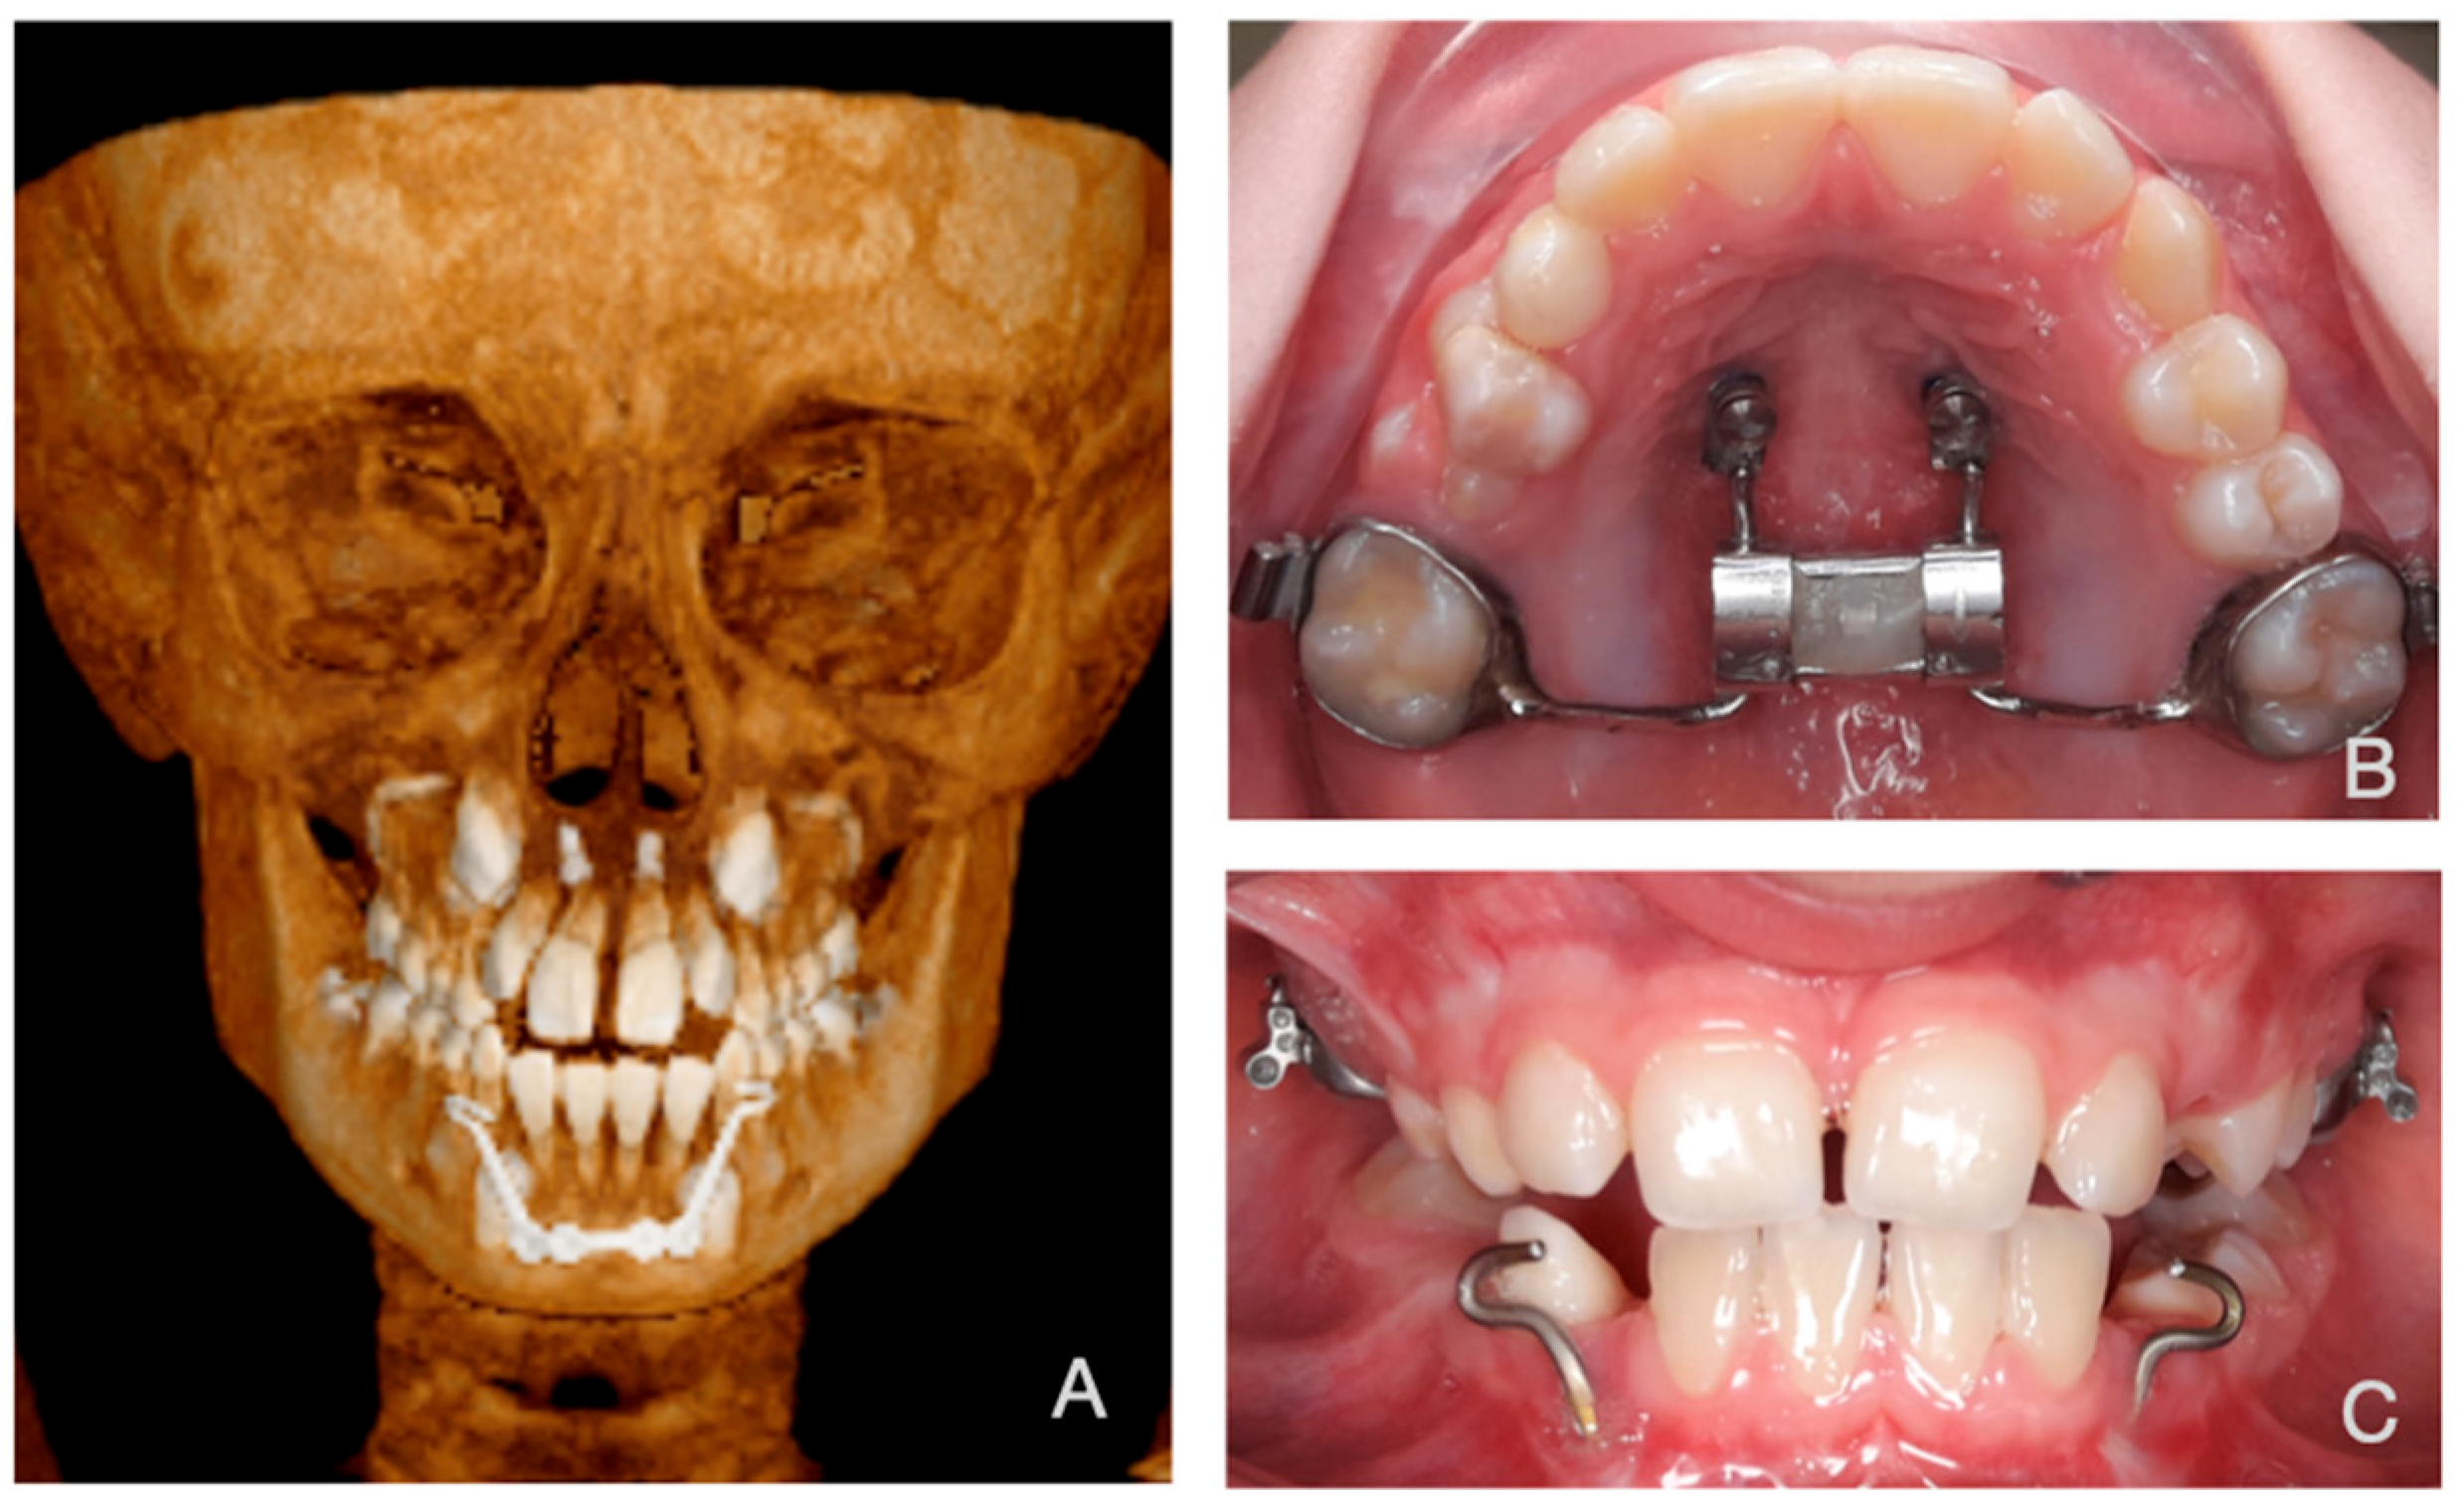

2.3. Creating a Patient Specific 3D FE Model

2.5. Boundary Conditions

2.7. Force Simulation